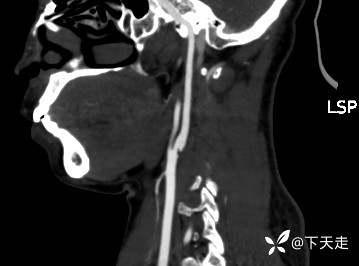

青鹊词 推荐青年女性,37岁,因不能言语就诊于耳鼻喉科,耳鼻喉科医生诊疗后建议神经内科就诊。

相关检验检查资料如下